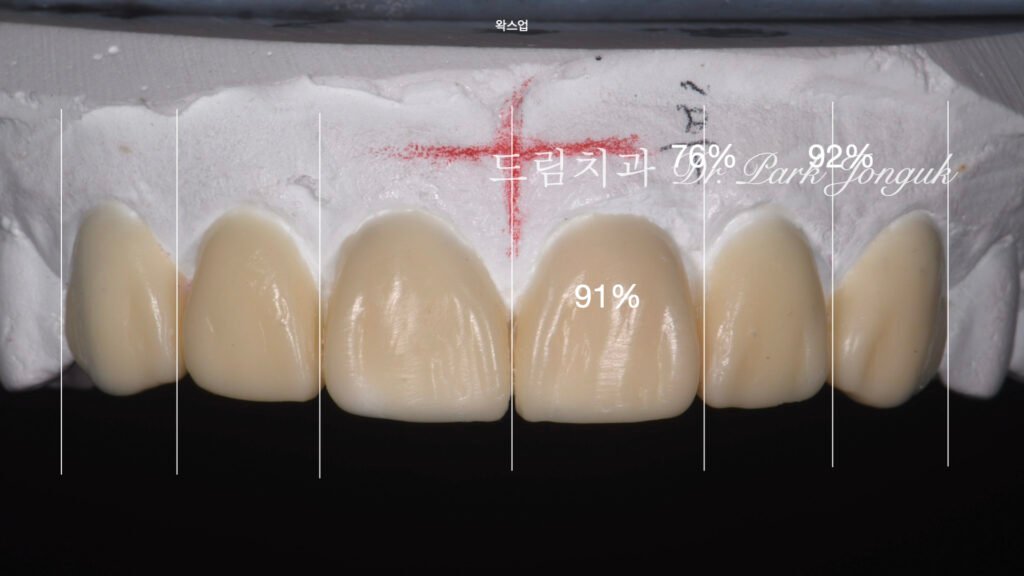

- Diagnostic Wax-up: 디지털 분석 데이터를 바탕으로 왁스 모델을 제작하여, 최종 결과물이 입술 라인과 이루는 조화를 미리 검증했습니다.

4. 핵심 기술: 보철물 간의 색상 매칭 (Shade Matching)

가장 큰 기술적 도전은 **’크라운과 라미네이트의 색을 똑같이 맞추는 것’**이었습니다.

- 재질의 차이: 크라운은 지대치를 완전히 덮는 두께를 가지며, 라미네이트는 치아 앞면에 붙는 0.1~0.3mm의 얇은 막입니다.

- Handmade Build-up: 기계 절삭 방식으로는 이 차이를 극복하기 어렵습니다. 숙련된 기공사와 전문의가 협업하여 세라믹 파우더를 층층이 쌓아 올리는 핸드메이드 빌드업 방식을 통해, 서로 다른 두께에서도 빛이 동일하게 반사되도록 광학적 성질을 맞추었습니다.